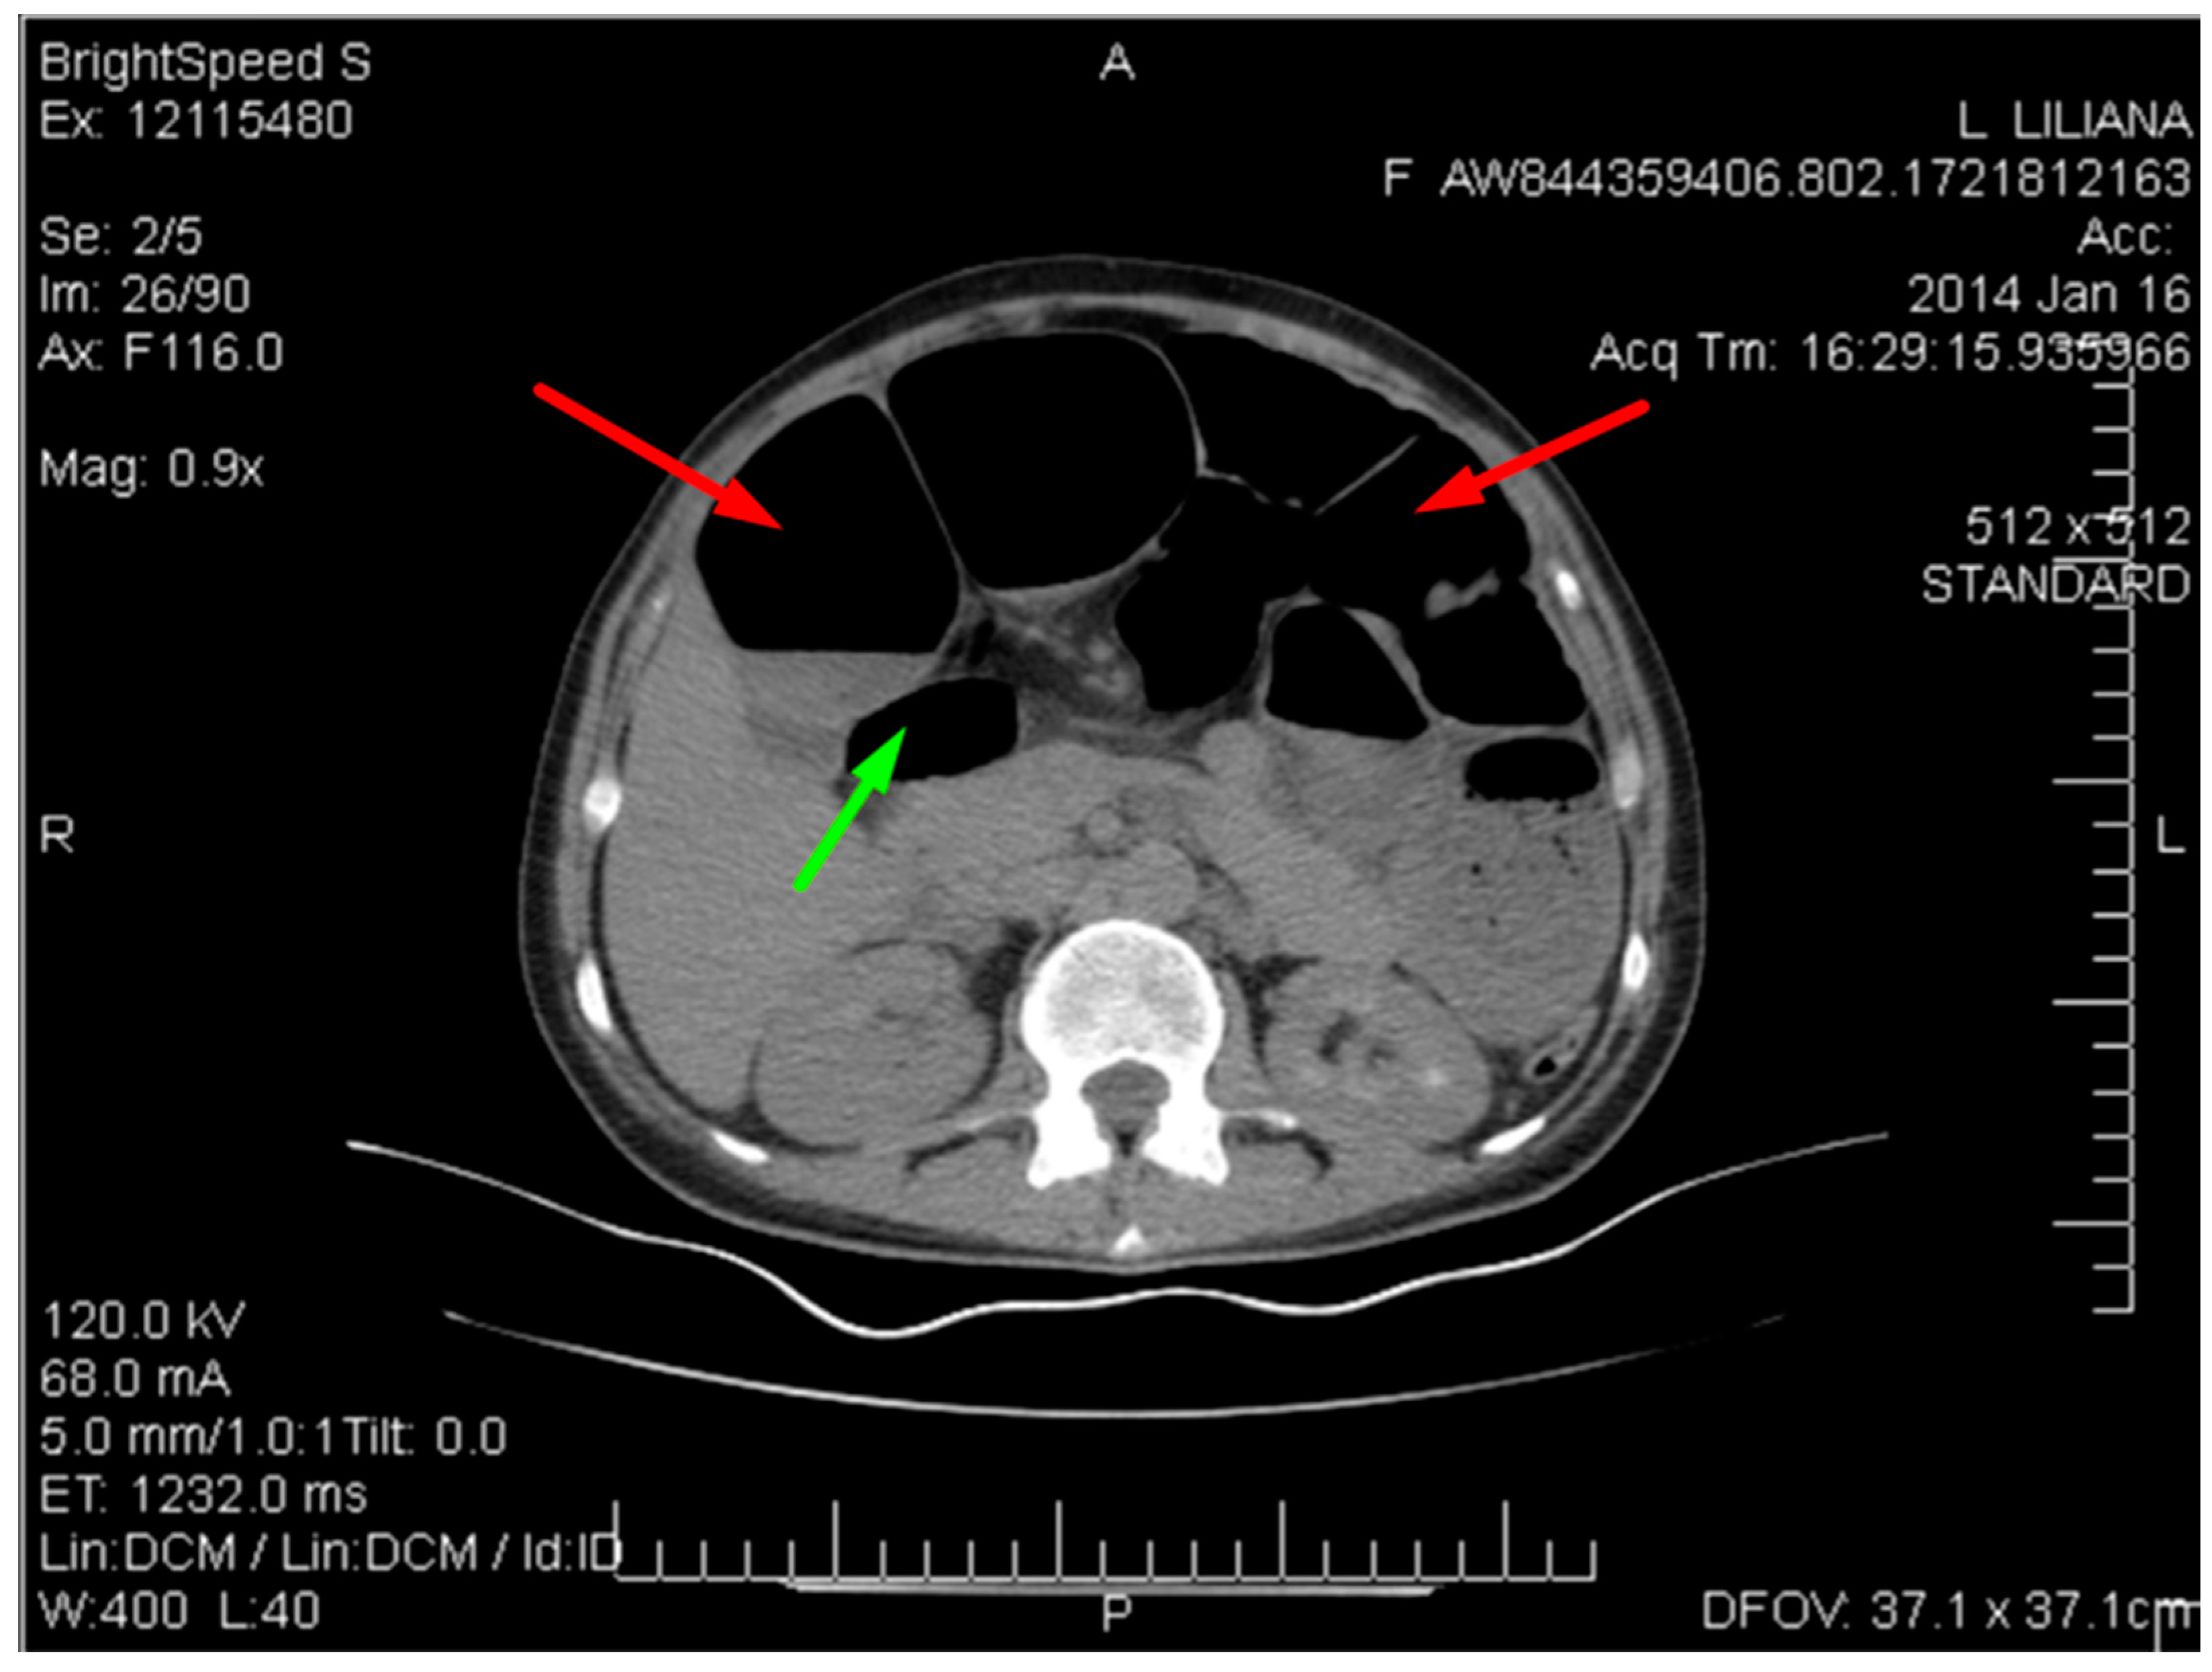

Figure 4 below shows multiple dilated loops of the small bowel with air.

Figure 4.

CT image of multiple dilated loops of small bowel with air (red arrows), and fluid (green arrow).

This distension is seen in many cases of small bowel obstruction, leading to the buildup of gas and fluid in the proximal segments. The absence of air in the distal bowel segments further supports the diagnosis of obstruction.

Figure 5 shows the spiralling appearance of the mesenteric vessels.

Figure 5.

CT image of the “Whirlpool sign”— spiralling appearance of the mesenteric vessels (red arrow) suggestive of a small bowel volvulus.

The CT scan revealed distention of the small intestine and detected an ileal loop that appeared looped around a blood vessel, validating the diagnosis of an intestinal volvulus.

The USG findings, in conjunction with the X-ray and contrast-enhanced CT, were crucial in detecting the intestinal obstruction produced by the volvulus and provided guidance for the eventual surgical operation. The integration of these visual tools allowed for a thorough evaluation, facilitating prompt and efficient handling of this intricate situation.